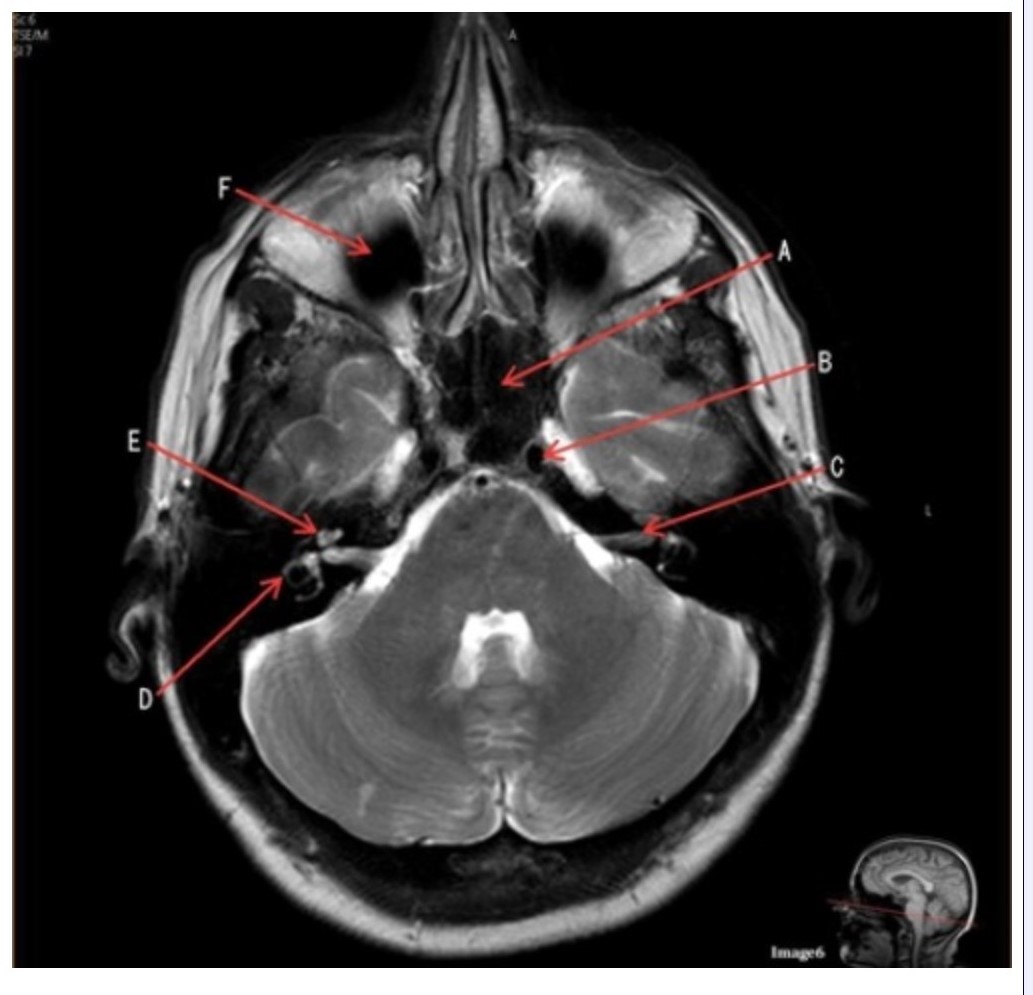

Letter A in Image 6 is pointing to:

A. Maxillary sinus

B. Sphenoid sinus

C. Frontal sinus

D. Internal carotid artery

Letter D in Image 6 is pointing to:

A. 7th cranial nerve

B. Cochlea

C. Trigeminal nerve

D. Semicircular canal

Letter C in Image 6 is pointing to:

A. 7th cranial nerve

B. Cochlea

C. Trigeminal nerve

D. Semicircular canal

Letter B in Image 6 is pointing to:

A. Maxillary sinus

B. Sphenoid sinus

C. Vertebral artery

D. Internal carotid artery

Letter F in Image 6 is pointing to:

A. Maxillary sinus

B. Sphenoid sinus

C. Frontal sinus

D. Optic chiasm

Letter E in Image 6 is pointing to:

A. 7th cranial nerve

B. Cochlea

C. Trigeminal nerve

D. Semicircular canal

Image 6 is an example of a _____ weighted sequence acquired in the _______ imaging plane.

A. T1; Axial

B. T1; Coronal

C. T2; Axial

D. T2; Coronal

E. STIR; Axial